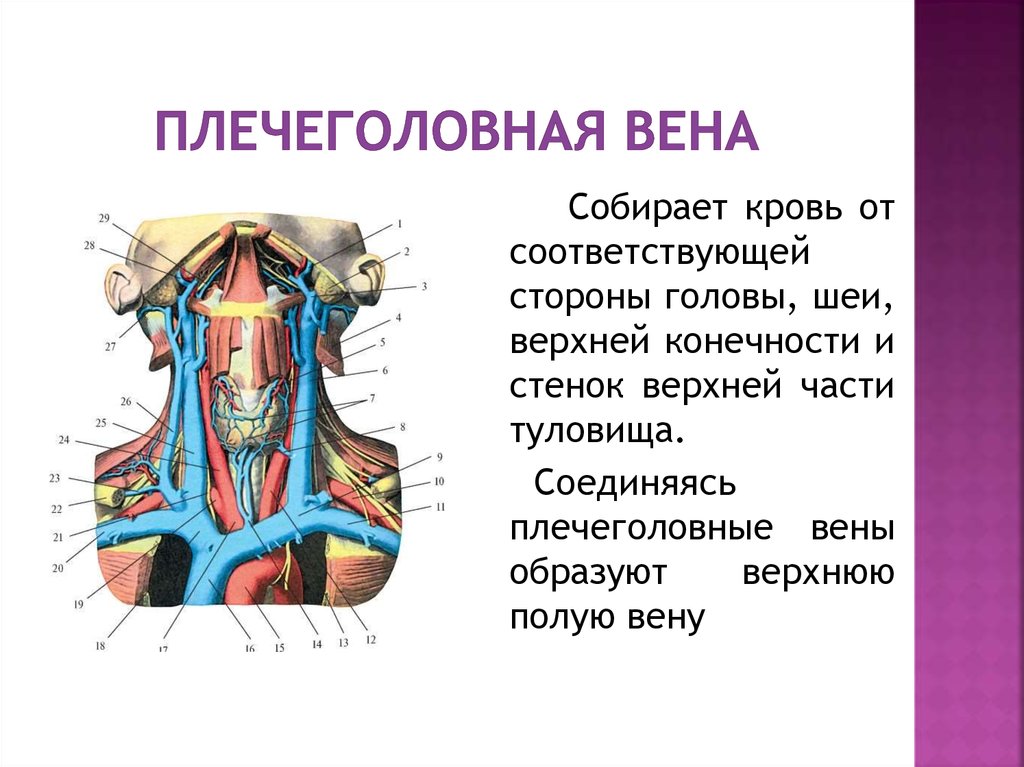

Анатомия внутренней яремной вены: КТ изображения